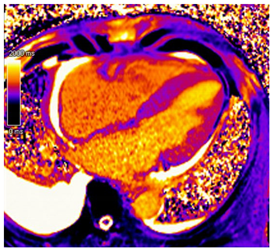

In addition to providing an accurate structural and functional assessment of cardiac chambers in IOC, CMR can quantify cardiac iron overload. Stored iron molecules in the form of hemosiderin act as small magnets when placed in a strong magnetic field, which shortens the relaxation time of tissue protons by disrupting their coherence. This can be measured more specifically as a T2*, which is the half-life time of signal intensity decay obtained using a gradient echo rather than a spin echo in T2 []. T2* is inversely proportional to the tissue iron contact. T2* measured within the interventricular septum is considered highly representative of global myocardial iron and has prognostic implications, as discussed below [,,].

T1 mapping is complementary to T2* and was shown to be concordant []. Native T1 time will be shortened with iron overload. Studies suggest that while T1 time may be more sensitive for cardiac iron content, it is less specific as it can be affected by myocardial fibrosis and fat [,]. Patchy areas of LGE can be seen secondary to replacement fibrosis []. In individuals with β-thalassemia major and myocardial iron overload, ECV was found to be increased and associated with a history of heart failure []. Key CMR findings in IOC are summarized in Table 3.

CMR can identify preclinical iron overload and enable early initiation of iron-chelation therapy. T2* can be used to risk stratify patients with IOC. T2* less than 20 ms is considered the threshold for myocardial iron overload. Values less than 20 ms were found to correlate with a reduction in LVEF, and values less than 10 ms were found to be associated with a higher risk of developing heart failure and arrhythmias in prospective studies of individuals with β-thalassemia major [,,,]. T2* value, therefore, helps guide the intensity of chelation therapy and is followed up to ensure improvement and response to therapy [].